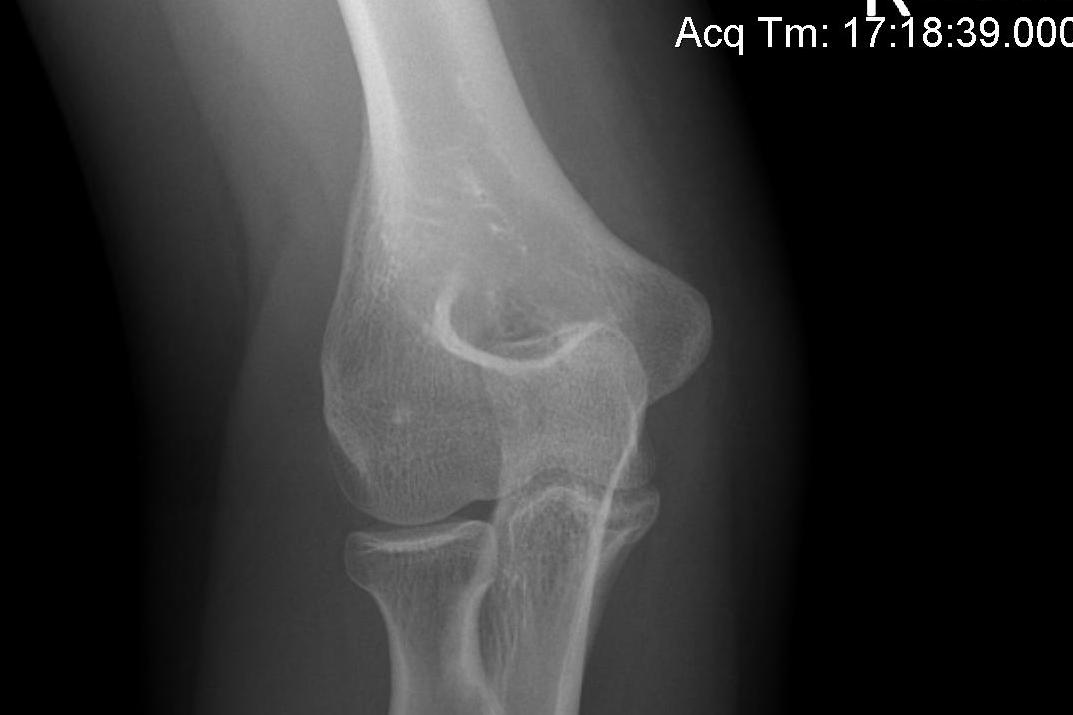

AP X-ray

Baumann's Angle

Technique

- angle between longitudinal axis humerus and capitellar physis

- should equal uninjured side

- 75o normal

Cubitus varus

- varus malposition > 81°

Cubitus valgus

- < 70o

Bony landmarks

In extension

- medial / lateral epicondyle and olecranon all in a line

In flexion

- medial / lateral epicondyle with olecranon from equilateral triangle